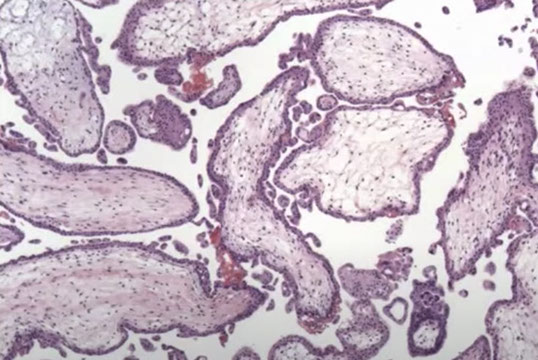

Hydropic Abortus

Presents as missed abortion c declining hCG levels

- grossly tissue scant, fetal parts usually not visible

- villi are uniform, round and occasionally fibrotic

- stromal vessels are rare and nonbranching, can have nRBCs

- trophoblastic hyperplasia is rare, but when present is polar

IHC: (+) p57 villous stromal cells and cytotrophoblasts

Genes: are diploid or aneuploid, occasionally triploid

Px: no inc risk of persistent dz